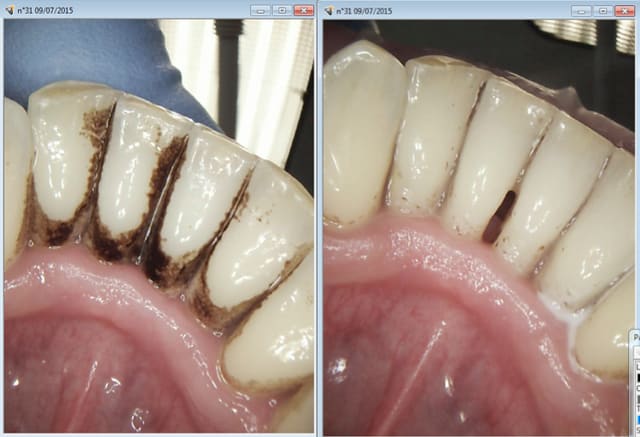

Ce type de traitement foireux c'est tous les jours que j'en vois aujourd'hui encore : bingo !

Capture d e cran 2015 07 10 20.01 - Eugenol